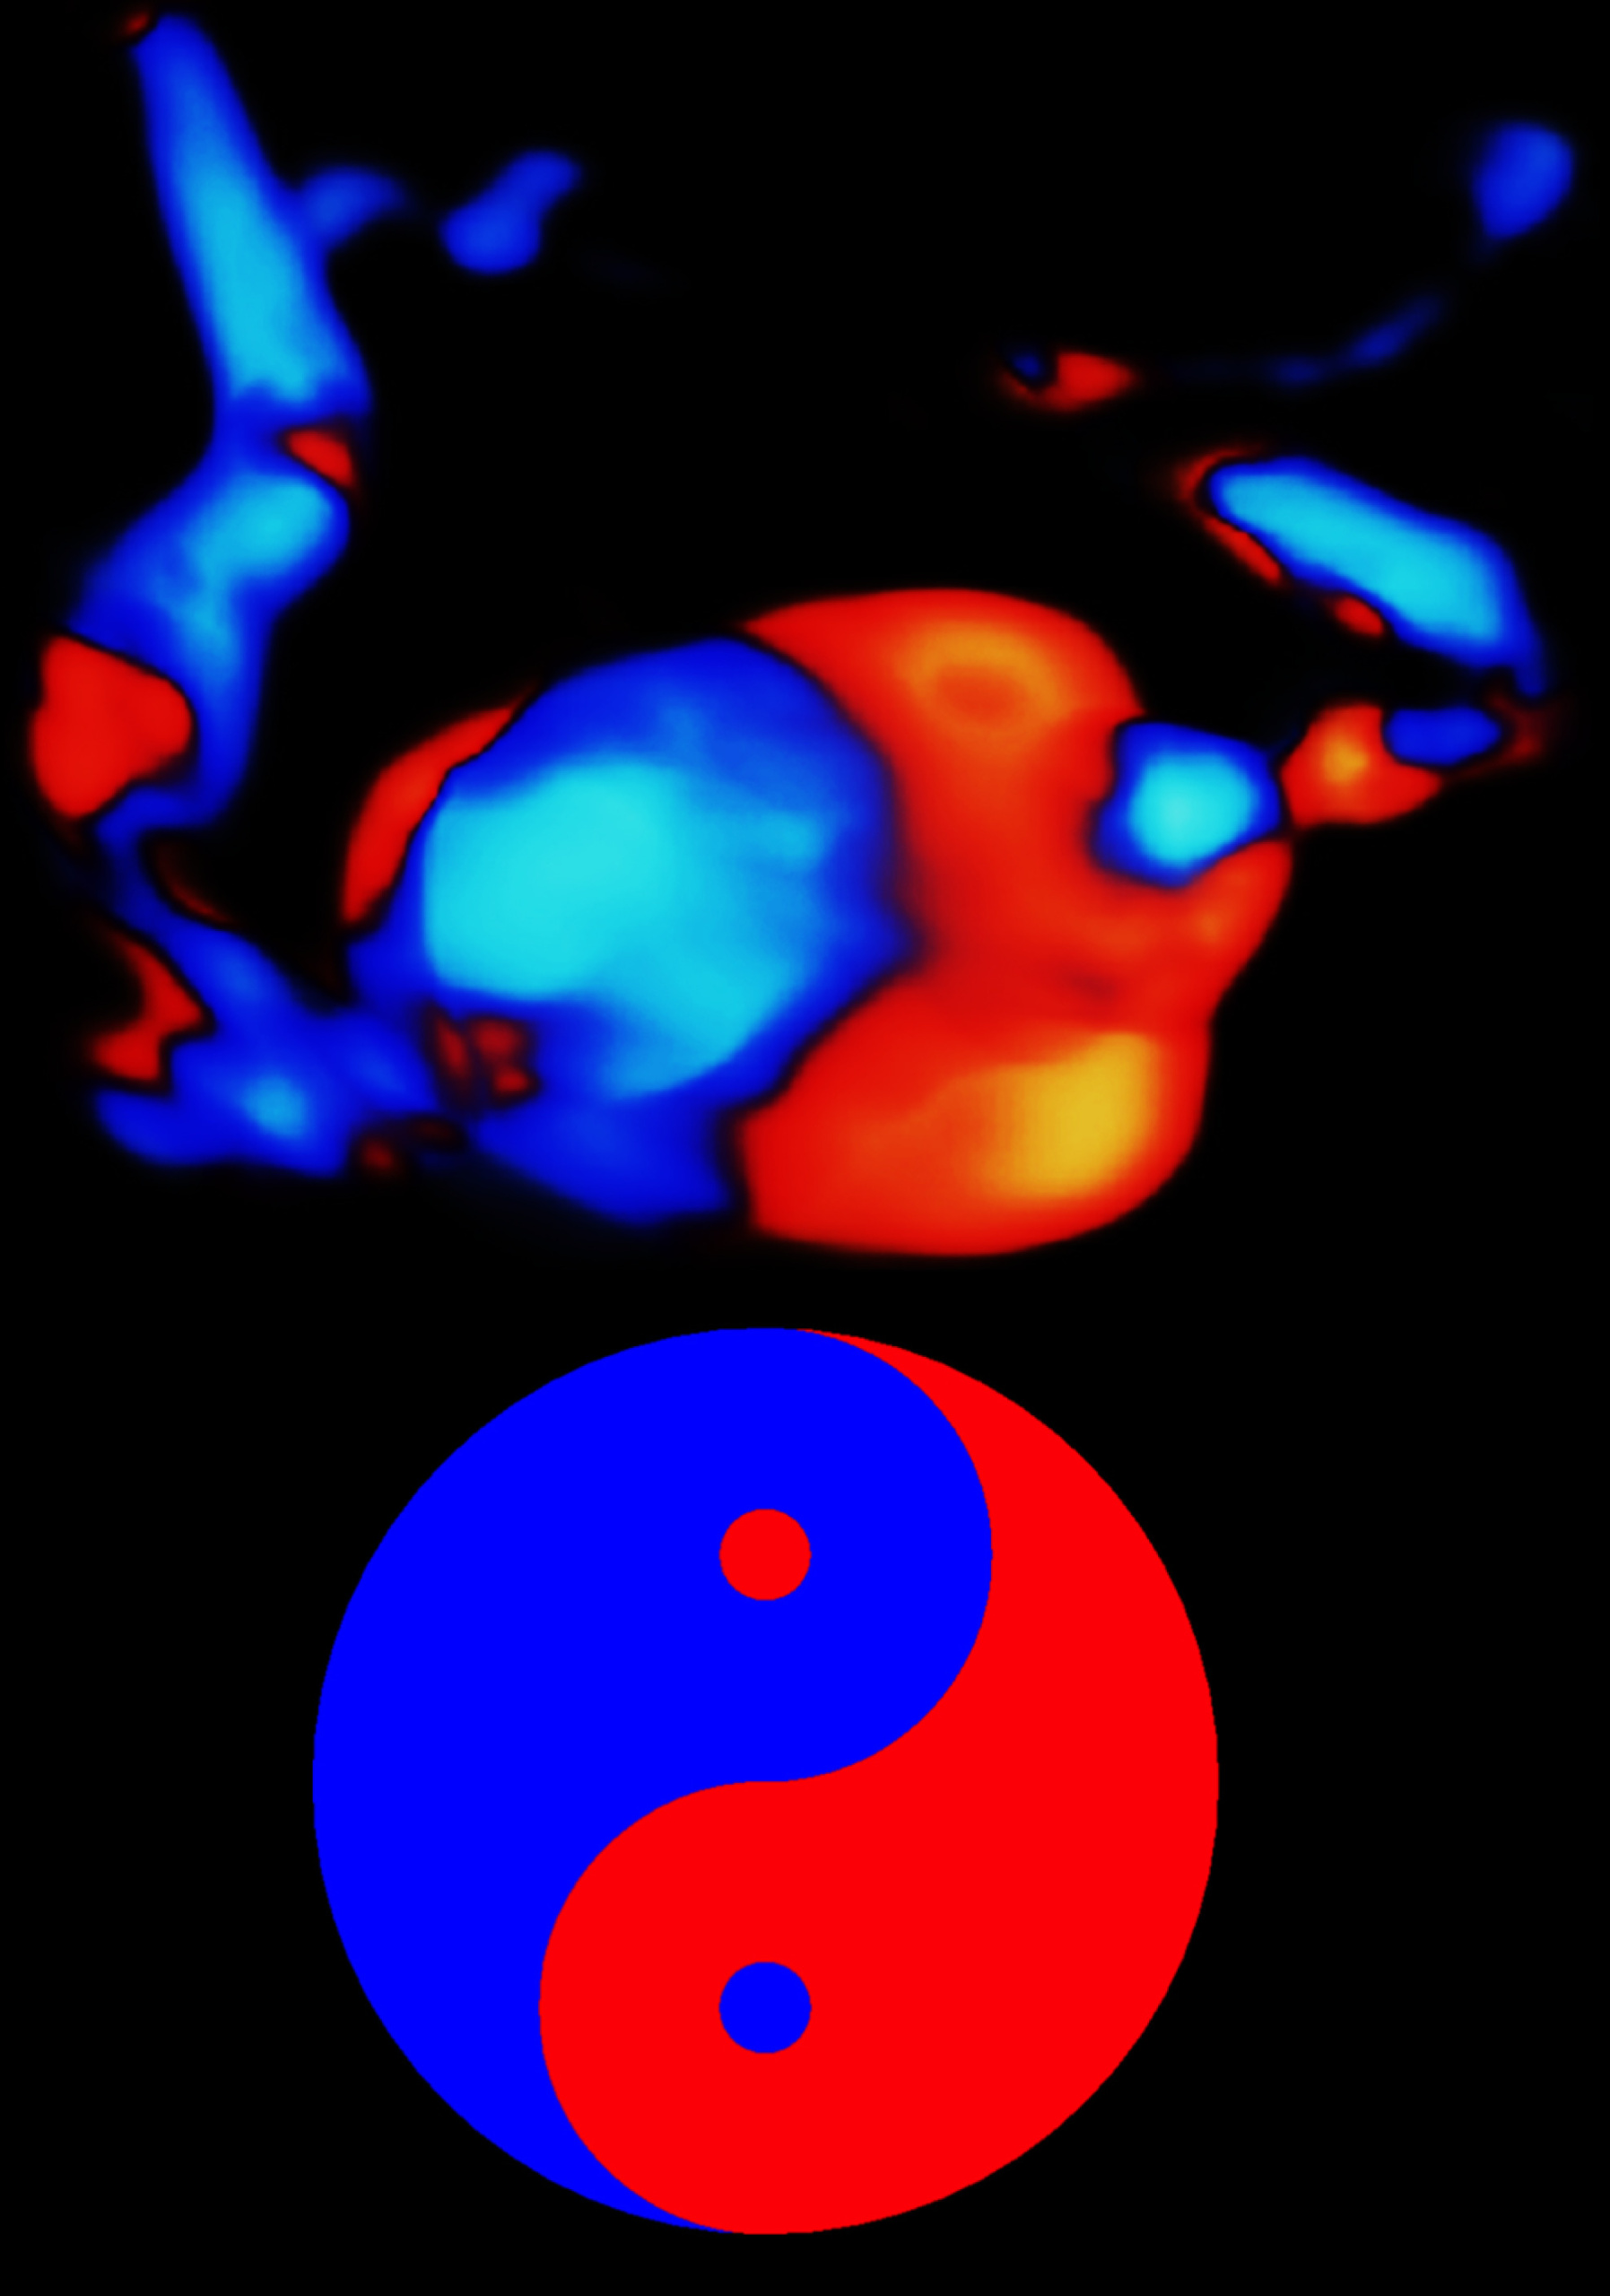

Hysterosalpingo‐lidocaine‐foam sonography combined with power Doppler imaging (HyLiFoSy‐PD) in tubal patency assessment: ‘flaming tube’ sign